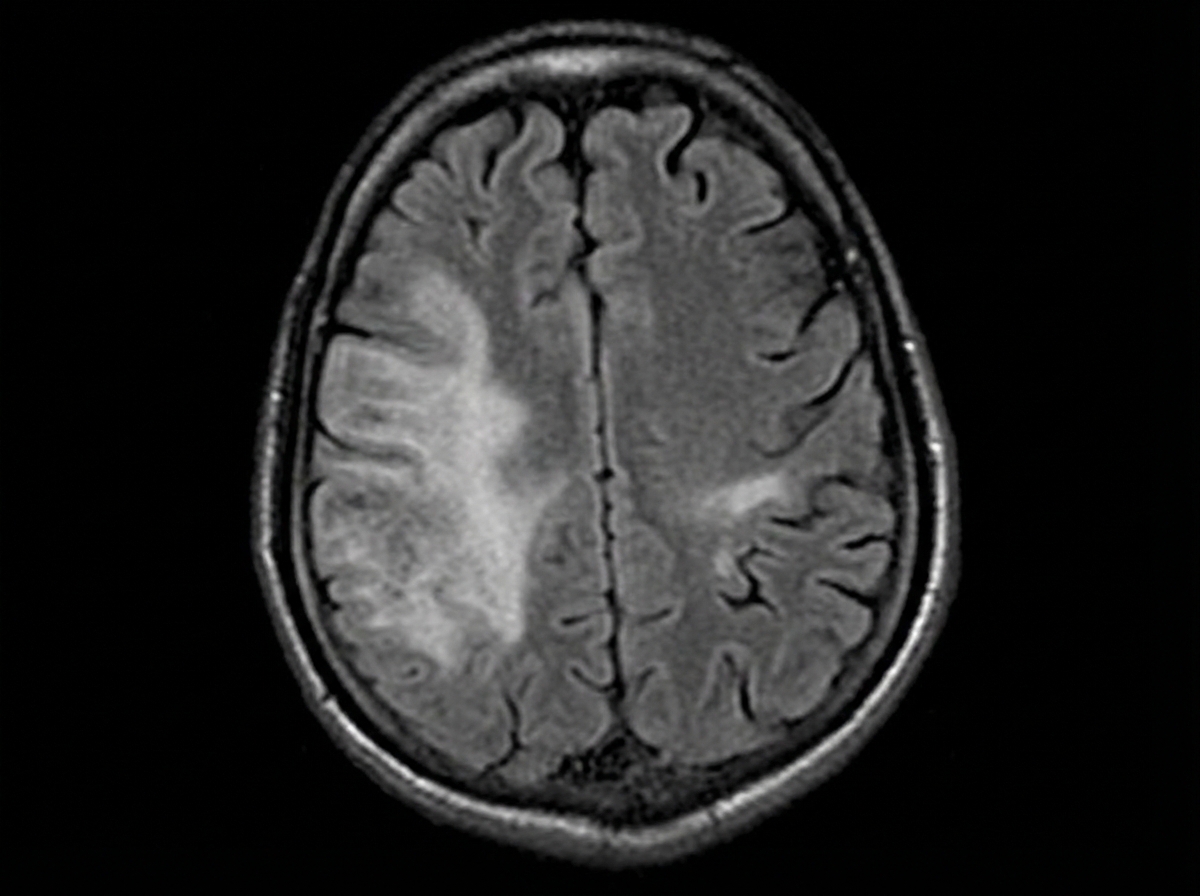

A 35-year-old woman with a history of Crohn disease presents for a follow-up appointment. She says that lately, she has started to notice difficulty walking. She says that some of her friends have joked that she appears to be walking as if she was drunk. Past medical history is significant for Crohn disease diagnosed 2 years ago, managed with natalizumab for the past year because her intestinal symptoms have become severe and unresponsive to other therapies. On physical examination, there is gait and limb ataxia present. Strength is 4/5 in the right upper limb. A T1/T2 MRI of the brain is ordered and is shown. Which of the following is the most likely diagnosis?